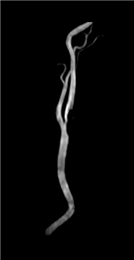

a:頸部MRA(3D-TOF MIP)

| a | 左頸動脈TOF法MRAのMIP像。内頸動脈側に狭窄が認められる。 |